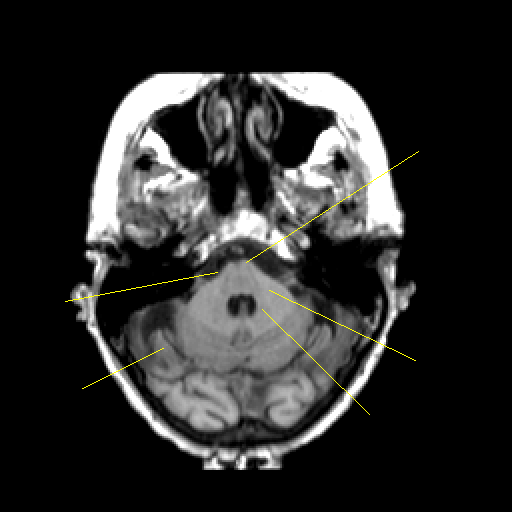

T1-weighted structural MR: Slice 13

Slice 13

Pointers

Labeled